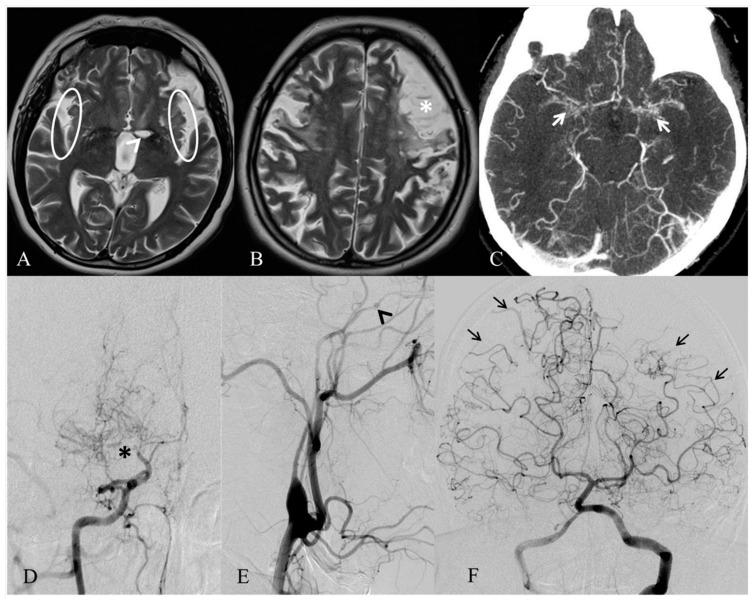

Moyamoya angiopathy (MA) is a cerebrovascular disease determining a progressive stenosis of the terminal part of the internal carotid arteries (ICAs) and their proximal branches and the compensatory development of abnormal "moyamoya" vessels. MA occurs as an isolated cerebral angiopathy (so-called moyamoya disease) or in association with various conditions (moyamoya syndromes) including several heritable conditions such as Down syndrome, neurofibromatosis type 1 and other genomic defects. Although the mechanism that links MA to these genetic syndromes is still unclear, it is believed that the involved genes may contribute to the disease susceptibility. Herein, we describe the case of a 43 years old woman with bilateral MA and peculiar facial characteristics, having a 484-kb microduplication of the chromosomal region 15q13.3 and a previously unreported 786 kb microdeletion in 18q21.32. This patient may have a newly-recognized genetic syndrome associated with MA. Although the relationship between these genetic variants and MA is unclear, our report would contribute to widening the genetic scenario of MA, in which not only genic mutation, but also genome unbalances are possible candidate susceptibility factors.

烟雾病(MA)是一种脑血管疾病,会导致颈内动脉(ICAs)末端及其近端分支进行性狭窄,以及异常“烟雾”血管的代偿性发育。MA 可作为一种孤立性脑血管疾病(所谓的烟雾病),或与多种情况相关(烟雾病综合征),包括几种遗传性疾病,如唐氏综合征、神经纤维瘤病 1 型和其他基因组缺陷。尽管将 MA 与这些遗传综合征联系起来的机制尚不清楚,但据信涉及的基因可能导致疾病易感性。在此,我们描述了一位 43 岁女性的病例,她患有双侧 MA 和独特的面部特征,存在染色体 15q13.3 区域的 484-kb 微重复和 18q21.32 区域的以前未报道的 786 kb 微缺失。该患者可能存在一种新发现的与 MA 相关的遗传综合征。尽管这些遗传变异与 MA 之间的关系尚不清楚,但我们的报告将有助于扩大 MA 的遗传情况,其中不仅基因突变,而且基因组失衡也可能是潜在的易感因素。